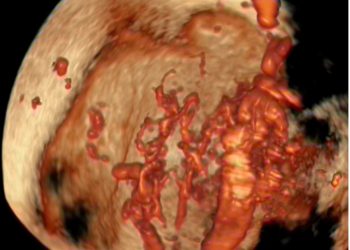

How To Do Marzo 2024: malformazioni uterine

Cari soci, questo mese un nuovo video "How to do", dedicato allo studio ecografico delle malformazioni uterine. Grazie a Ilaria...